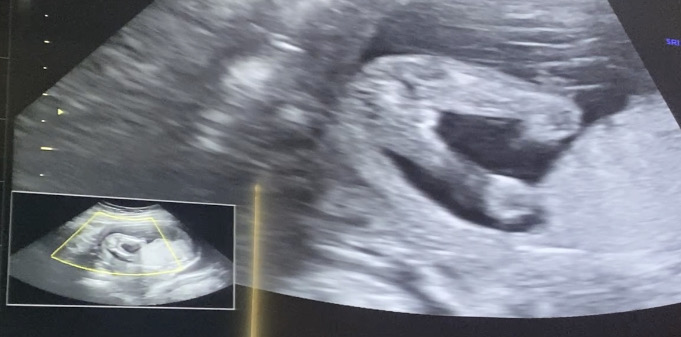

16주 다리 사이 초음파 성별 유추 부탁해요

병원에서는 95퍼 여자라고하고 챗 지피티는 남자아이라고하네요?! 여러분의 생각이 궁금합니다

16주 아들촘파에요 ㅋㅋㅋㅋㅋㅋ

딸같아용!저 딸인데 약간 비슷ㅎㅎ 아들은 독보적으로 큰것같아용ㅎㅎ

여자아기요